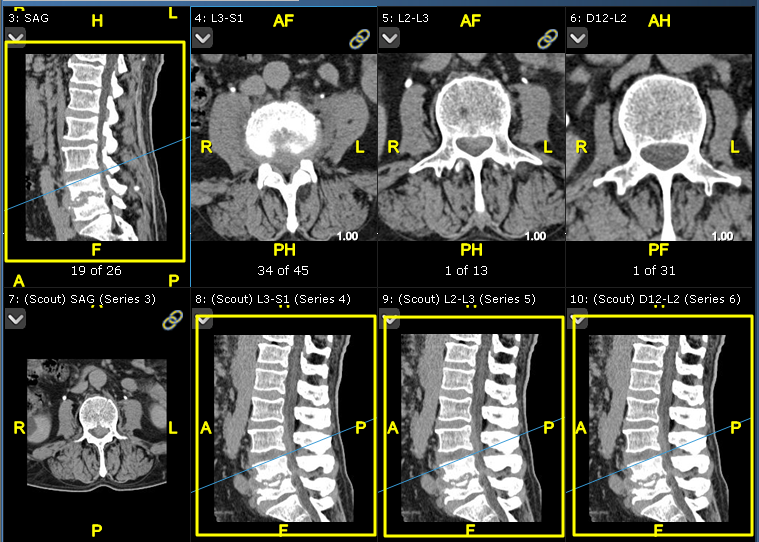

Εξέταση που δείχνει τέσσερις σειρές με κοινό πλαίσιο αναφοράς. Ανατρέξτε στη γραμμή που τέμνει τις εικόνες (επισημαίνεται).

Παράδειγμα εξέτασης με τέσσερις σειρές με κοινό πλαίσιο αναφοράς